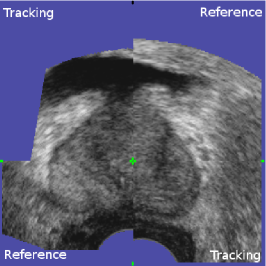

The first experiment evaluates the capacity of the kinematic probe movement model to estimate a probe position sufficiently close to its real position with respect to the gland. For this test, 786 registrations of the biopsy volumes of 47 patients were performed with the corresponding panorama volumes. The registrations were then visually validated either by the clinician immediately after biopsy acquisition or off-line by one of the authors. This was carried out using a volume viewer that allows to overlay and to explore the reference and the tracking volume after application of the registration transformation (see Fig. 13). Note that the accuracy of a large and randomly chosen subset of the registrations classified as valid was evaluated to 0.8±plus-or-minus\pm0.5 mm, cf. the accuracy study presented in Sec. 6.2, which indicates that only few registrations were falsely identified as correct. In this study, 769 (97.8%percent\%) volumes were classified as valid, and 17 (2.2%percent\%) were classified as failures. The 17 failures occurred with volumes that did not contain enough information about the prostate, i.e. the tracked object was literally ”out of view”. This was caused by inadequate US depth or probe pressure (prostate capsule not visible) in 11 cases, partial probe contact with the rectum in 1 case, extremely lateral volumes containing only a small part of the prostate in 4 cases and an incomplete panorama in 1 case. Note that the failures were not caused by patient movements.

Refer to caption

Figure 13: Viewer for visual validation. The viewer shows transverse (a), sagittal (b) and coronal cuts (c) simultaneously. The registration volumes are overlaid: the upper-left and lower-right corners of each view show the tracking volume, while the lower-left and upper-right corners show the reference volume. The green cut point is the 3D point where the three image planes intersect. The user can move the cut point freely in each view, allowing him to explore the entire volume (changing the point in one view changes the spatial position of the other two views).